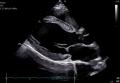

「Vivid Pioneer」は、これまで検査者が手作業で行っていた血流解析をAIが自動で行い、短時間で安定した測定プロセスを提供します。また、心臓の主要な部位(左心室と左心房)の動きや形を三次元で自動分析し、検査者間の標準化を支援します。そのほか、次世代の画像エンジン機能により、細部の見やすさ(空間分解能)や色の見やすさ(カラー感度)が向上し、より高精度な心臓の立体画像を描出します。

[画像2:

AIが血流を自動解析